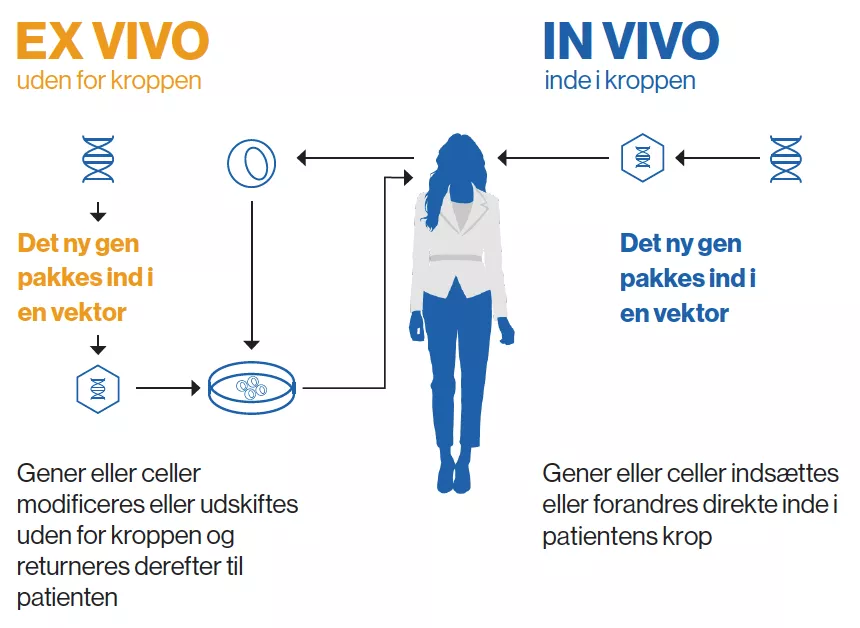

Celle- og genterapier bygger på grundig forskning, der bygger på mange årtiers videnskabelige fremskridt. De centrale redskaber og teknologier er blevet afprøvet og raffineret af utallige eksperter – først i laboratoriet og sidenhen i klinikken. Ved celleterapi dyrkes eller modificeres cellerne uden for kroppen, før de indsprøjtes i patienten, hvor de udvikler sig til et "levende lægemiddel". Ved genterapi udskiftes, inaktiveres eller indføres generne i celler – enten uden for eller inde i kroppen – for at behandle en sygdom. Nogle behandlinger kvalificerer sig som både celle- og genterapier.